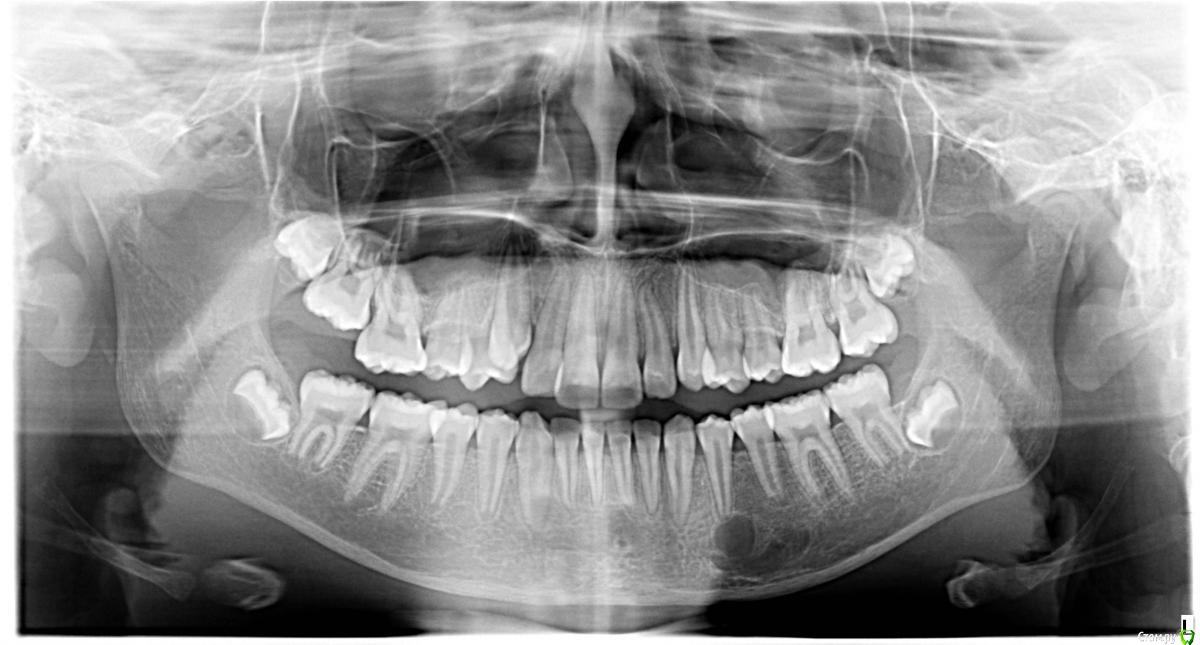

bullbull Опубликовано 17 ноября, 2015 Поделиться Опубликовано 17 ноября, 2015 При ОПТГ и последующей КТ обнаружена полость в кости с мягкотканным содержимым (300-400 HU). Клинических проявлений никаких. Пациентка 13 лет, планируется постановка брекетов.Что это может быть? Может стоит направить в ЧЛХ? Ссылка на комментарий

hemchik Опубликовано 17 ноября, 2015 Поделиться Опубликовано 17 ноября, 2015 Вроде там есть камерность , что характерно для амелобластомы. Если есть подозрение на опухоль нужно делать пункцию. Ссылка на комментарий

девять Опубликовано 23 ноября, 2015 Поделиться Опубликовано 23 ноября, 2015 Тень проецируется в области выхода 3-ей ветви, если бы было новообразование были бы явления сдавления нерва.По снимку муфтообразного утолщения нет.Нет ли гемангиом на лице.Наверно отправить на консультацию в члх. Ссылка на комментарий

bullbull Опубликовано 25 ноября, 2015 Автор Поделиться Опубликовано 25 ноября, 2015 Лицо не изменено, клинических проявлений ни со стороны зубов, ни со стороны лица нет.От консультации у ЧЛХ отказались. Без консультации мы, в свою очередь, отказались устанавливать брекеты. Ссылка на комментарий